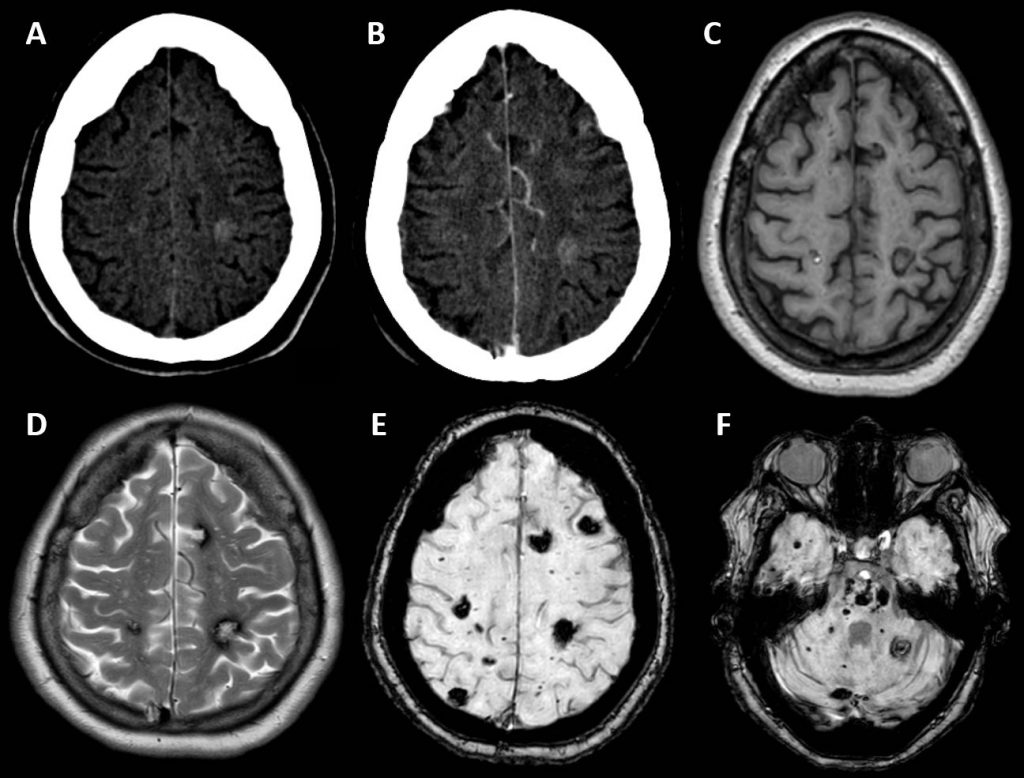

Síndrome de malformación cavernomatosa múltiple familiar con mutación genética KRIT1.

Síndrome de malformación cavernomatosa múltiple familiar con mutación genética KRIT1.

Los cavernomas son malformaciones vasculares en cerebro y médula, constituidas por agrupaciones de vasos inmaduros dilatados sin tejido neural normal interpuesto.

El síndrome de malformación cavernomatosa múltiple familiar únicamente constituye entre el 5-15% de las malformaciones vasculares cerebrales. Aunque puede ser esporádica en 1/3 de los casos, generalmente tiene una herencia autosómica dominante. Las mutaciones genéticas más frecuentemente descritas son las siguientes: KRIT1 (53-65%), CCM2 (20%), PDCD10 (10-16%).

Para el diagnóstico por imagen, la técnica de elección es la RM donde son de gran utilidad las secuencias de eco de gradiente y susceptibilidad magnética que hacen mucho más visibles los milimétricos focos hipointensos secundarios a residuos de hemosiderina.

Ante múltiples hemorragias cerebrales se debe realizar el diagnóstico diferencial fundamentalmente entre: angiopatía amiloide (edad avanzada, localización corticosubcortical), encefalopatía hipertensiva (antecedente de HTA, localización ganglios de la base y fosa posterior), daño axonal difuso (antecedente traumático, localización unión sustancia blanca-gris) y metástasis hemorrágicas (antecedente neoplásico, realce con contraste).